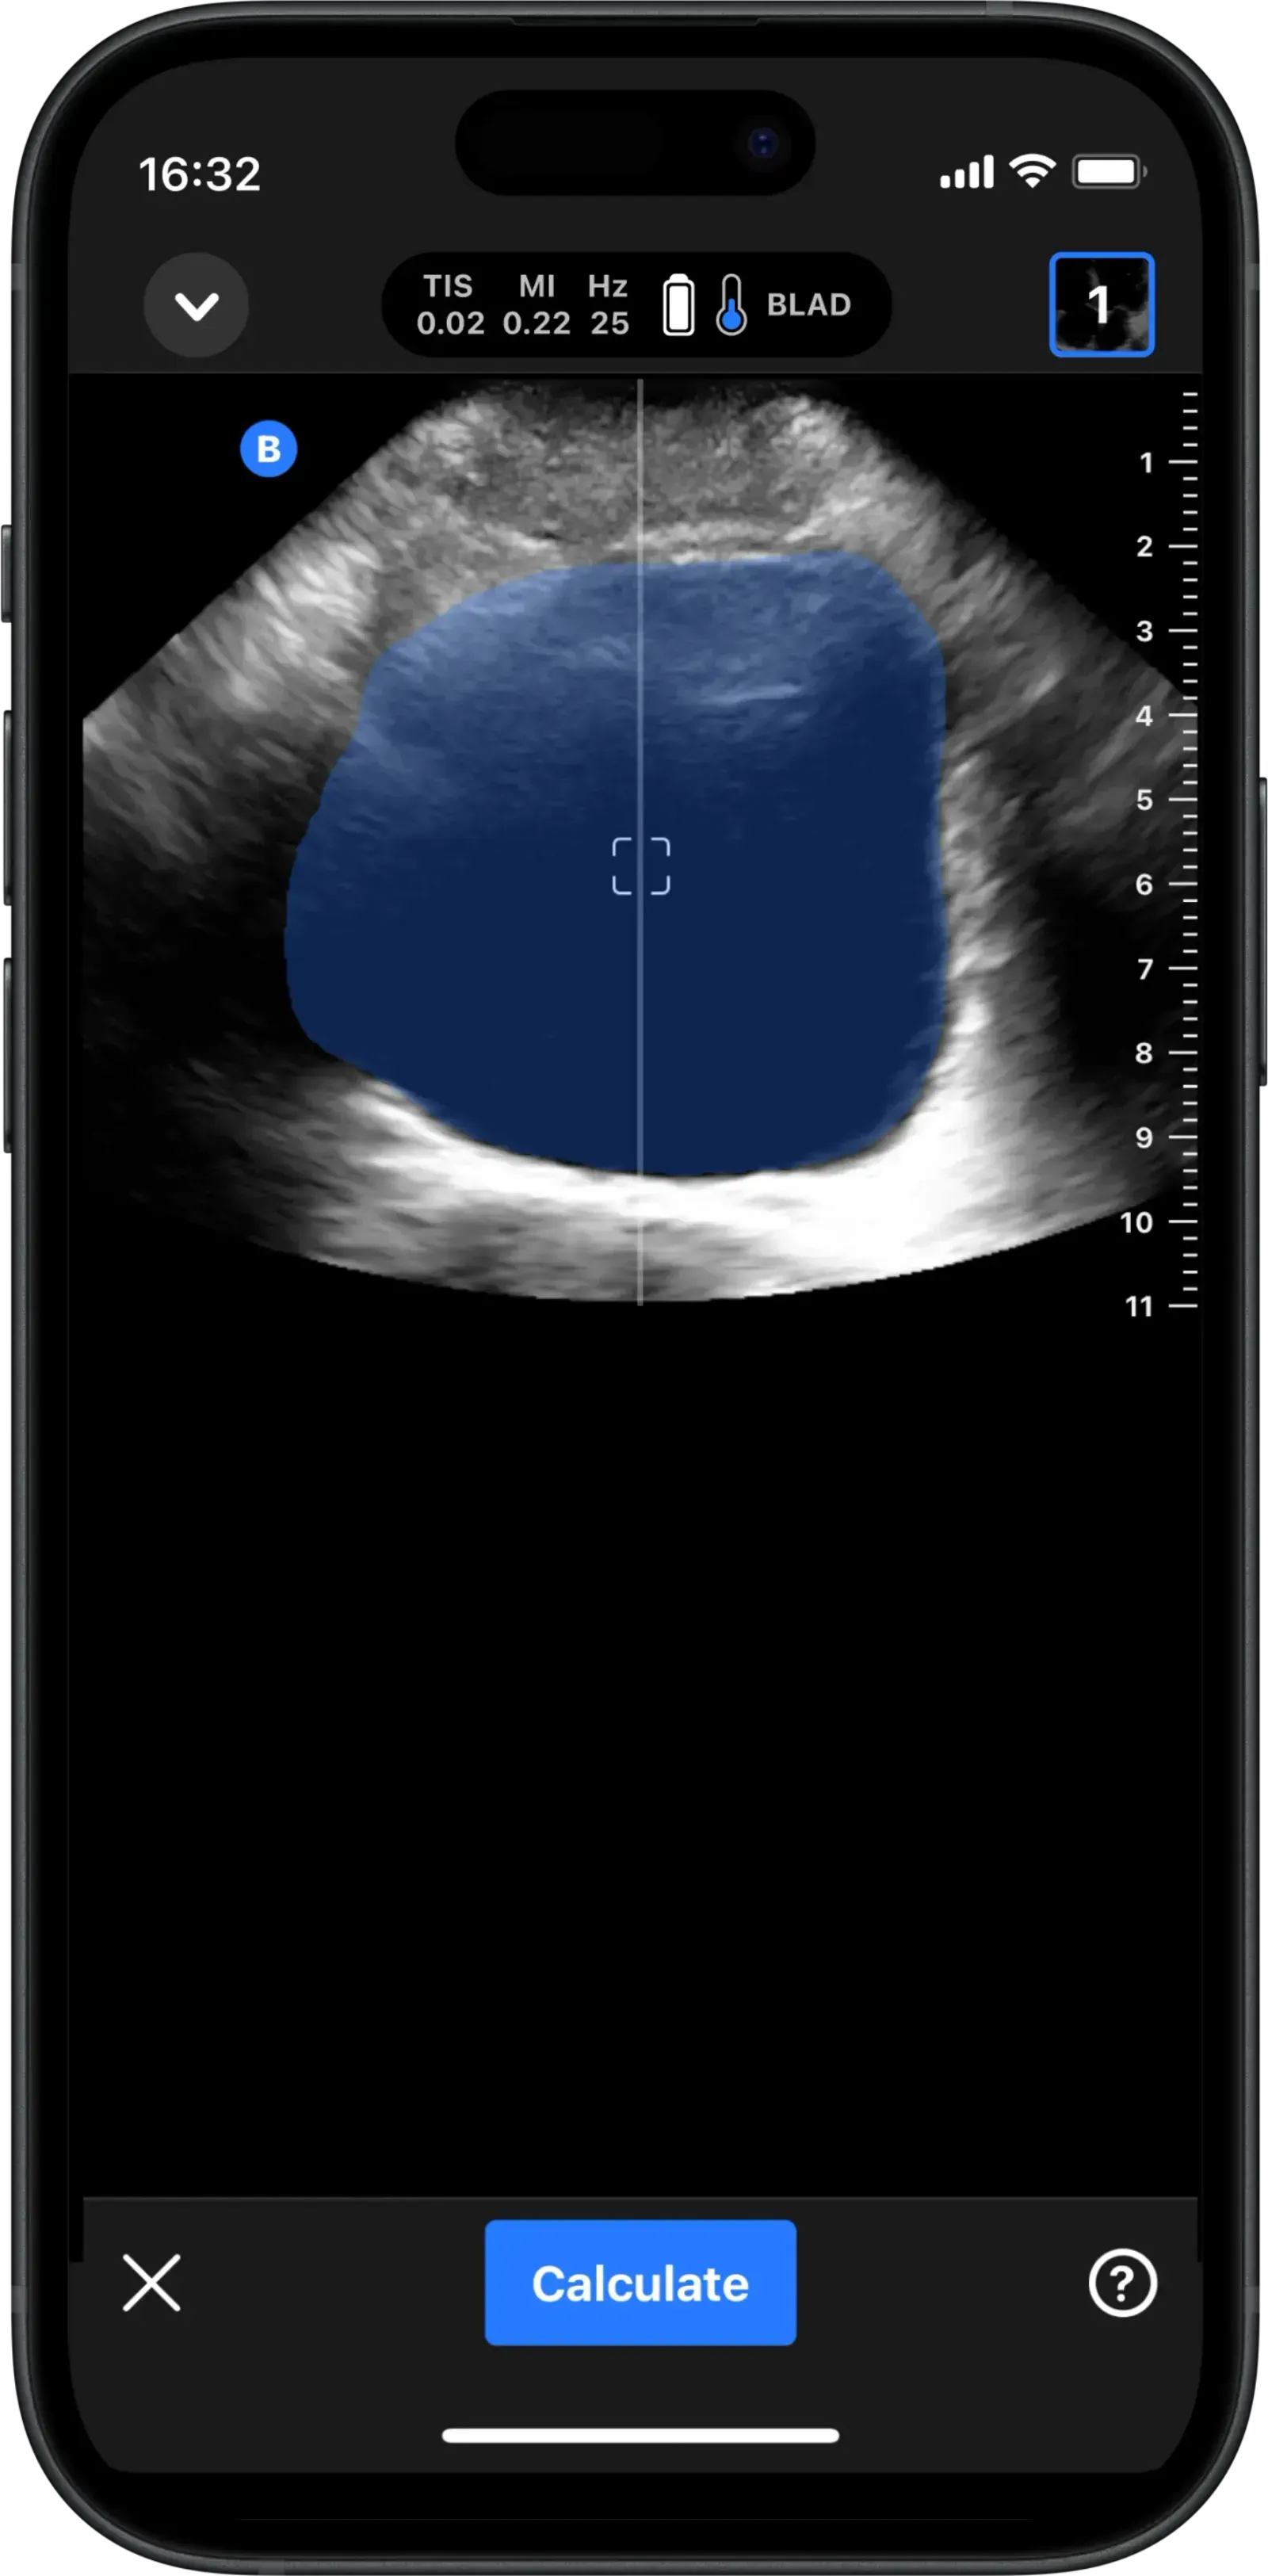

Calculate bladder volume to support urinary retention management.